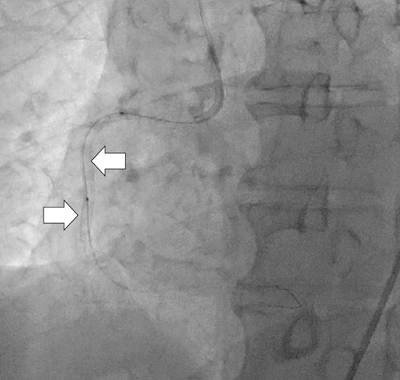

より正確に,より短時間にPCIを実施するためには,PCI術中にデバイスを正確に観察できる高画質な透視像を提供することが必須条件となる。当社では,従来のパターン認識フィルタ(DPRF),背景圧縮処理(ADCF)に加えて,東芝のX線装置の新画像処理コンセプト“Pure Brain”の核となる新しいノイズ低減フィルタ“Super Noise Reduction Filter(SNRF)”を導入した。

SNRFは,周辺画素を含めた独自のノイズ識別方法により,X線量を増加させずに透視像および撮影像の大幅なノイズ低減が可能となるフィルタである。また,リカーシブフィルタのような過去画像を使用した画像処理ではないため,透視でも残像による動体ボケは生じない。本システムでは,SNRFを組み込むことで,残像を生じさせずに,空間解像度を保ったままノイズを低減するという高画質な透視像および撮影像を実現した。図2に透視像の例を示す。右冠動脈に3.0mm×18mmおよび3.0mm×30mmのDriverステントが連続して留置されている様子(→)が明瞭に観察できる。

図2 透視像例(Driverステント:3mm×18mmと3mm×30mm)

(画像ご提供:高瀬クリニック様)